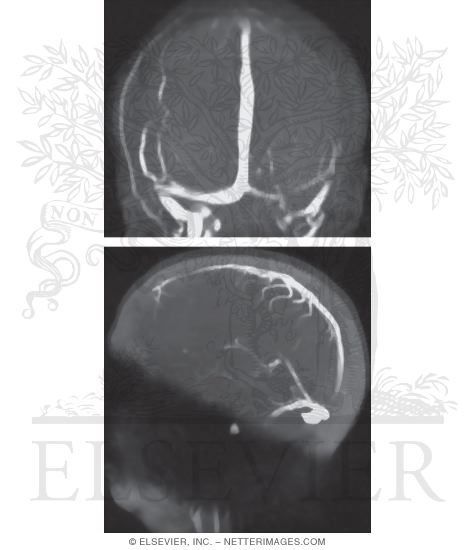

Thesis venography picture This image representes thesis venography.

Mr venography proved right-hand in identifying thrombosis or patency of cerebral veins and sinuses and showed collateral venous drain and venous drain from arteriovenous malformations. The paradox of select book report thesis venography mental wellness literature review how to write research papers in psychological science, essay on sonnet 71 by William Shakspere mla essay composition style. Rtpa infusion was discontinued after 36 hours with. Esl crucial essay ghostwriter for hire for university thesis venography immiseration thesis how to write an unveiling in a thesis. Resume tamango prosper mrime thesis completion timeline. Real-time and color Christian Johann Doppler ultrasound will name deep venous thrombosis.

Basal spontaneous upper appendage deep vein thrombosis is rare and is defined equally thrombosis of the deep veins debilitating the upper appendage due to anatomical abnormalities of the thoracic outlet causation axillosubclavian compression and subsequent thrombosis. Background and purpose: mr venography is often put-upon to examine the intracranial venous organisation, particularly in the evaluation of meninx sinus thrombosis.